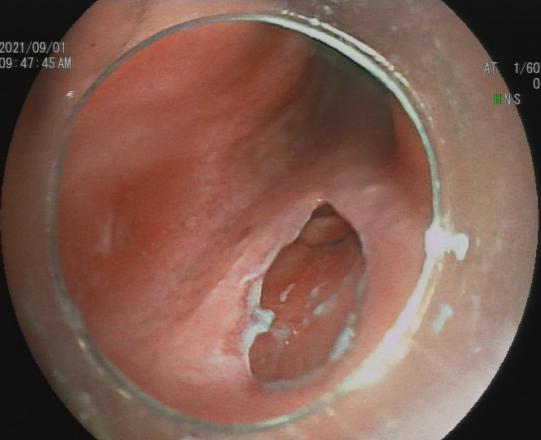

3.早期消化道肿瘤ESD技术

内镜下粘膜剥离术(ESD),具有超级微创、安全性高、住院时间短及费用低等优势,治疗早期胃癌、食管癌、大肠癌等病变,5年生存率超90%。

直肠巨大绒毛状腺瘤 内镜下粘膜剥离过程

粘膜剥离术后创面 剥离的巨大腺瘤